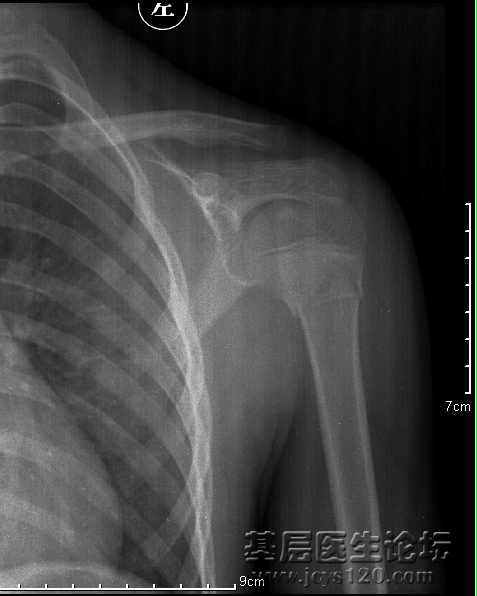

倒霉啊。先说说患者:男,14岁(有怀疑),摔伤

第一次是肩关节正位,是我一个同事照的:

显示肱骨外科颈骨折,患肢悬吊固定一周前来复查,这回是肱骨正侧位:

我照的,正位好说,侧位选取穿胸位,连续失败了8次,第九次严格说也不成功,算了,让大家随便说吧。